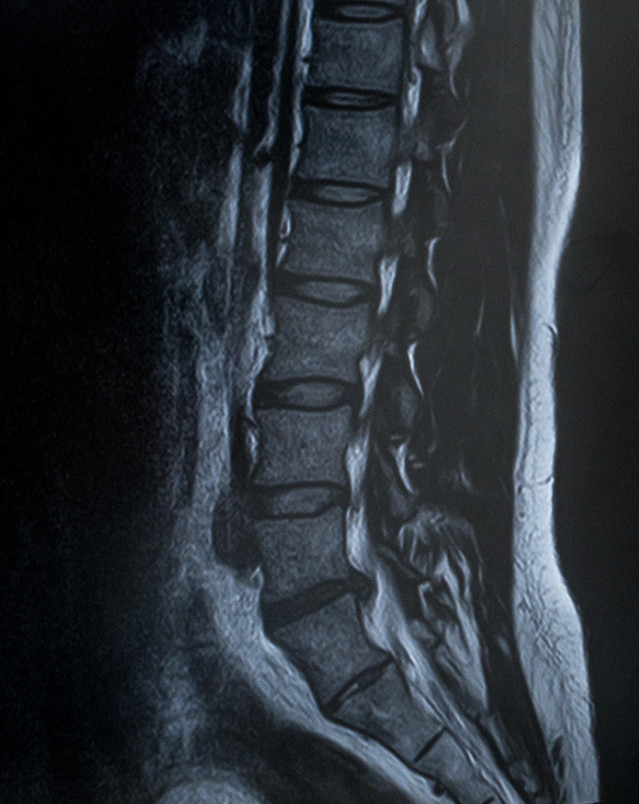

• 腰部脊柱管狭窄症

脊柱管は背中の中央を貫く[神経の通り道]です。

この脊柱管が腰の所で何らかの原因で狭くなり中を通っている神経が圧迫されることによって腰痛やシビレを起こします。

特徴的な症状は[間欠性跛行]で、歩いているうちに足に痛みやシビレが出て歩きにくくなりますがしゃがんだり座ったりすると症状が無くなりまた歩けるのが特徴です。